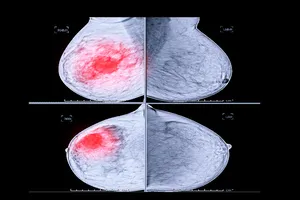

1. 유방에 만져지는 멍울이 있는 경우

유방을 만져보았을 때 딱딱하거나 부드러운 멍울이 느껴진다면 맘모톰 수술을 통해 정확한 진단과 치료를 받을 수 있습니다.

3. 조직 검사를 위해 조직 채취를 하는 경우

유방에 발생한 미세 석회화나 다른 병변에 대한 정확한 진단을 위해 조직 검사가 필요할 때 맘모톰을 이용하여 조직을 채취할 수 있습니다.